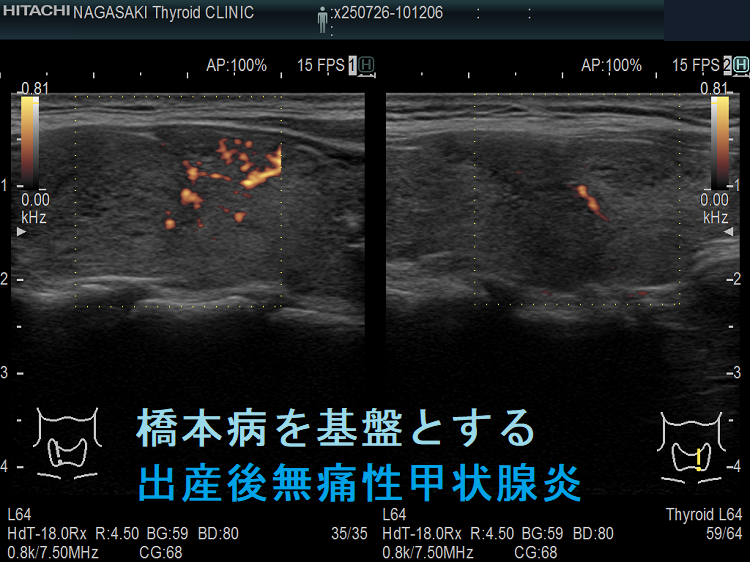

橋本病を基盤とする出産後無痛性甲状腺炎(水平断) ドプラーモード;無痛性甲状腺炎であるため、内部血流は少ない。

橋本病を基盤とする出産後無痛性甲状腺炎下甲状腺動脈の収縮期最大血流速度(ITA-PSV);無痛性甲状腺炎であるため、下甲状腺動脈の収縮期最大血流速度(ITA-PSV)は低値